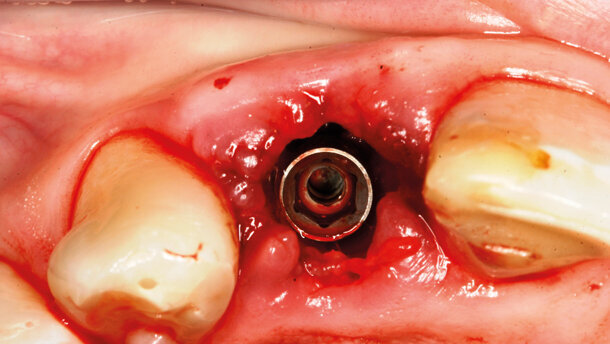

Dopo l’anestesia locale, si procede all’estrazione atraumatica dell’elemento, prestando particolare attenzione alla conservazione della corticale vestibolare (Fig. 5), condicio sine qua non per cui l’impianto non può essere inserito e deve essere rimandato. Si opta per un’estrazione con tecnica piezoelettrica (Surgybone, Silfradent, Italia), utilizzando un apposito inserto come sindesmotomo per lussare l’elemento dentale senza compromettere la corticale ossea.

Dopo avere verificato l’integrità della corticale vestibolare6, si procede con l’inserimento più palatale dell’impianto (SPI, Alpha-Bio Tec, Israele) (Fig. 6) e nella stessa seduta si rileva l’impronta con tecnica a cucchiaio chiuso per realizzare un provvisorio avvitato immediato (Figg. 7, 8, 9). Dopo circa due ore si procede alla consegna del manufatto, opportunamente scaricato dai contatti sia in centrica che in eccentrica (Figg. 10, 11) per evitare microtraumi che potrebbero inficiare l’osteointegrazione. Il paziente viene dimesso con la seguente terapia farmacologica: antiinfiammatorio al bisogno, antibiotico per ulteriori quattro giorni (una compressa ogni 12 ore in associazione ai fermenti lattici una volta al giorno) e disinfezioni del cavo orale con clorexidina diclugonato 0,12% due volte al giorno.